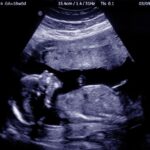

Ngôi thai là gì? Ngôi thai bất thường phải làm sao?

Bạn đang xem bài viết Ngôi thai là gì? Ngôi thai bất thường phải làm sao? tại mnkienhung.edu.vn bạn có thể truy cập nhanh thông tin cần thiết tại phần mục lục bài viết phía dưới. Tìm hiểu ngôi thai là gì là việc không kém phần quan trọng để quá trình sinh nở diễn ra […]